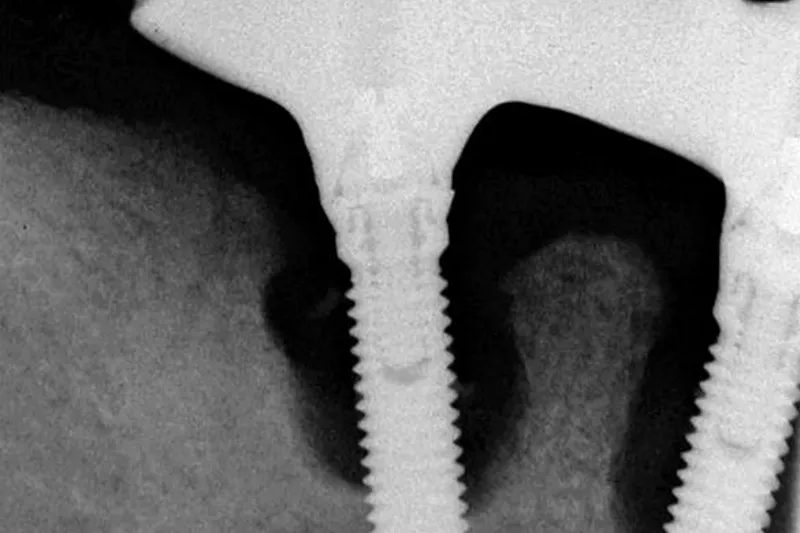

Mindst hvert fjerde implantat, der indsættes, vil udvikle peri-implantitis. Selvom denne tilstand overfladisk set kan minde om parodontitis, er den langt sværere at behandle med et forudsigeligt resultat, bl.a. fordi vi ikke har tilstrækkelig indsigt i de mikrobiologiske og immunologiske forhold omkring implantaterne. Dette har en tværfaglig forskergruppe fra Ann Arbor (Michigan, USA) nu rådet bod på med en opsigtsvækkende undersøgelse.

24 voksne patienter med peri-implantitis blev underkastet en grundig behandling, der bl.a. indebar lapoperation med indlæg af knoglemateriale og membran. Det fjernede granulationsvæv blev nedfrosset og senere undersøgt for forekomst af 10 forskellige leukocyt-typer samt en lang række inflammationsmolekyler.

Studiet inkluderer 24 forsøgsdeltagere med mindst et implantat diagnosticeret med peri-implantitis, dvs. poche over 5 mm med blødning. Implantaterne havde alle intraossøse knogledefekter, der berettigede til den udførte regenerative parodontalkirurgiske behandling. Studiets protokol inkluderede en afvigelse fra gældende retningslinjer, idet alle forsøgsdeltagerne fik ordineret 500 mg amoxicillin 3 x dagligt i 7 dage postoperativt.